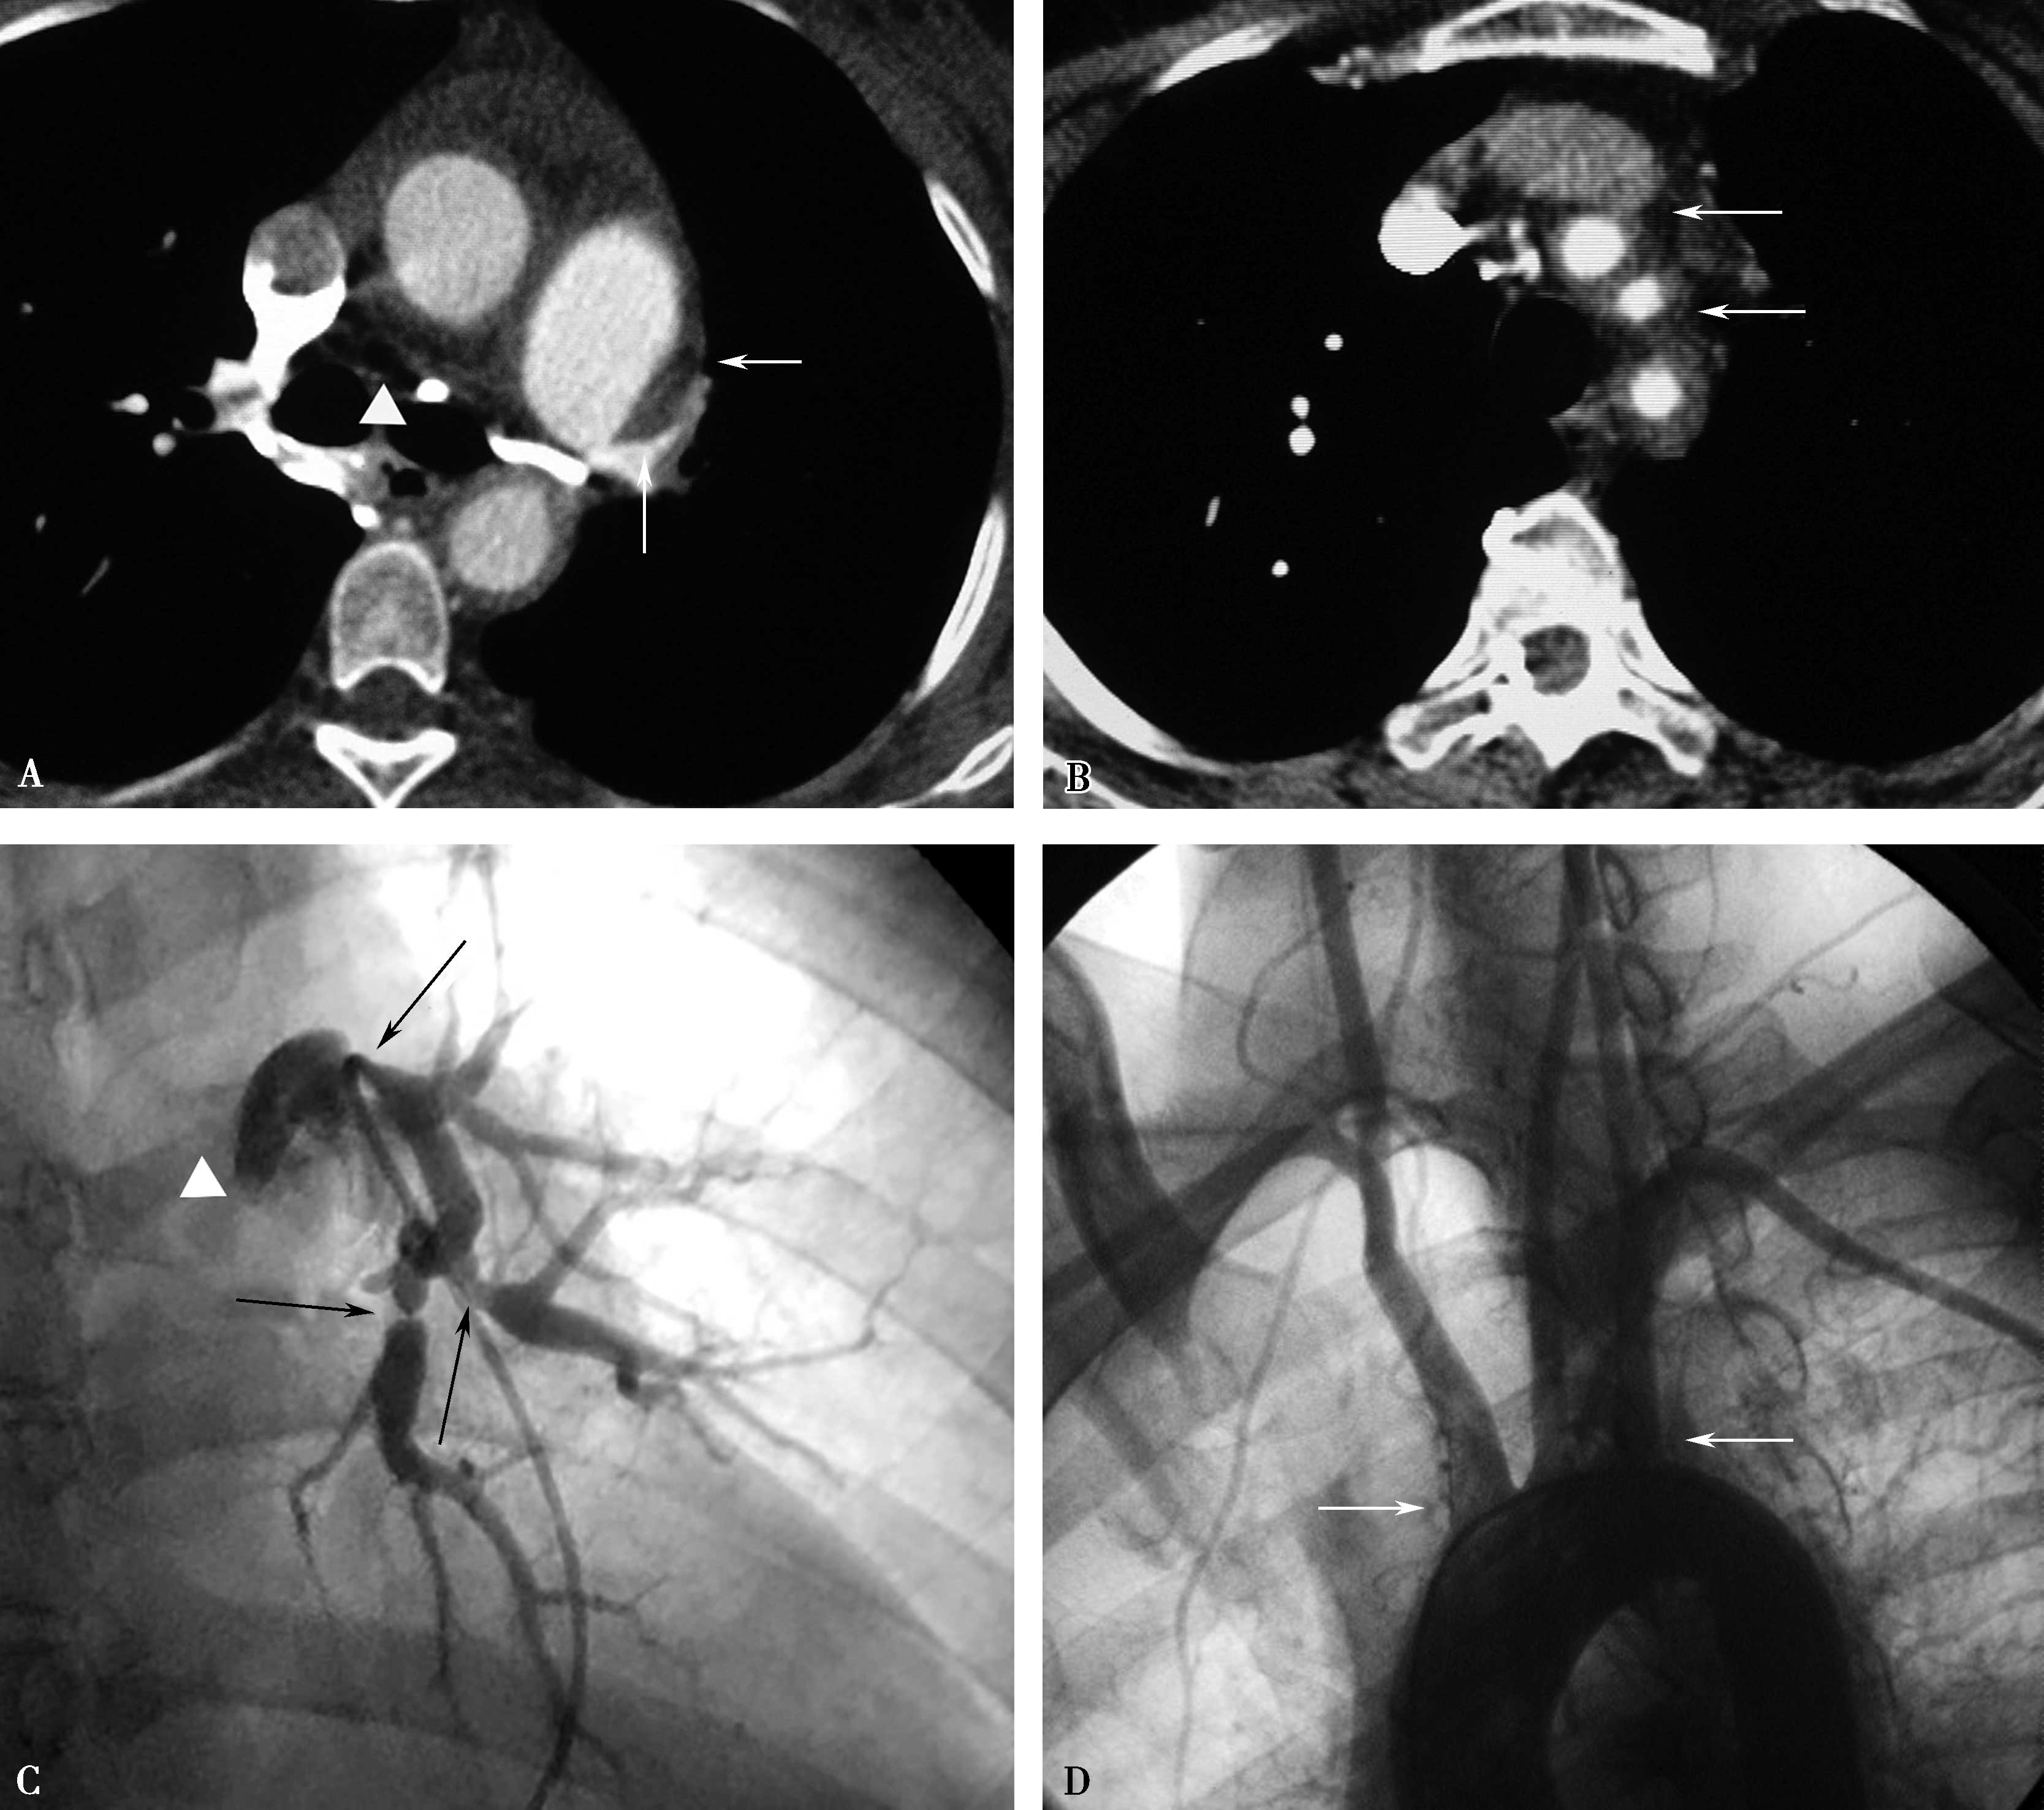

横断扫描是诊断检查基础(图8-5-2, 图8-5-3)。

图8-5-2 “肺动脉”型大动脉炎

AB.CT横断图像,右肺动脉闭塞(A↑),左锁骨下动脉闭塞、钙化(B↑);C.肺动脉造影,右肺动脉闭塞(↑);D.主动脉造影,左锁骨下动脉闭塞(↑)。诊断:“肺动脉”型大动脉炎。证实CT所见

图8-5-3 “肺动脉”型大动脉炎

A.CT横断图像,右肺动脉闭塞(▲),左肺动脉及分支多发狭窄-闭塞(↑);B.横断图像,左颈总动脉、左锁骨下动脉开口部管壁增厚(晕环征),管腔狭窄不明显(↑);C.肺动脉造影,右肺动脉闭塞(△),左肺动脉及分支多发狭窄(↑);D.主动脉造影,左颈总动脉、左锁骨下动脉开口部管壁僵硬,未见明显狭窄(↑)。CT诊断:“肺动脉”型大动脉炎